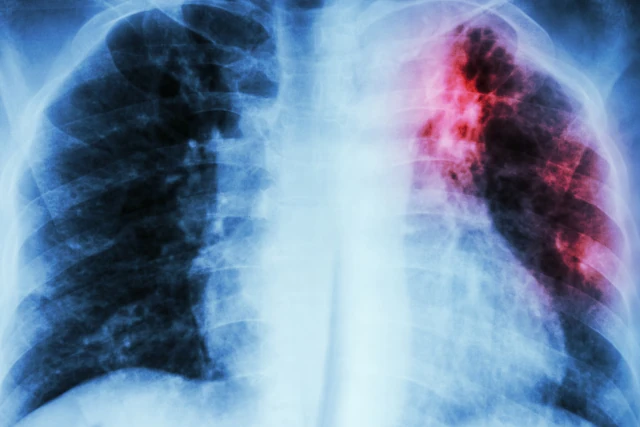

La tuberculose est une maladie contagieuse causée par une bactérie en suspension dans l’air qui affecte principalement les poumons. On estime qu’environ un quart de la population mondiale est atteint de tuberculose, mais seuls 5 à 10 % d’entre eux développent des symptômes.